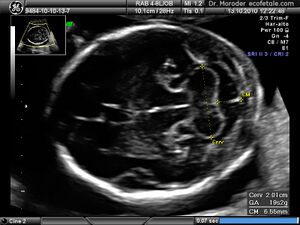

Congenital malformation, hereditary disorders, and acquired conditions can affect cerebellar structure and, consequently, cerebellar function. Unless the causative condition is reversible, the only possible treatment is to help people live with their problems.[21] Visualization of the fetal cerebellum by ultrasound scan at 18 to 20 weeks of pregnancy can be used to screen for fetal neural tube defects with a sensitivity rate of up to 99%.[22]